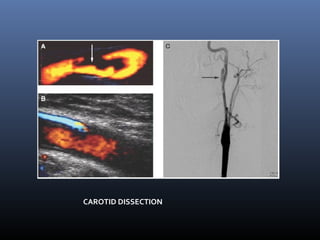

CAROTID DISSECTION

Dissection  Imaging techniqueof choice  MRA -2D TOF ,DSA- Gradual irregular tapering,stenosis, Distal emboli, psedoaneurysms Non contrast fat supressed T1 sequence at base of skull and neck- crescentic hyperintensity in vessel mura